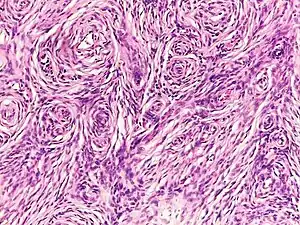

Neurofibromas arise from nonmyelinating-type Schwann cells that exhibit biallelic inactivation of the NF1 gene that codes for the protein neurofibromin.[3] This protein is responsible for regulating the RAS-mediated cell growth signaling pathway. In contrast to schwannomas, another type of tumor arising from Schwann cells, neurofibromas incorporate many additional types of cells and structural elements in addition to Schwann cells, making it difficult to identify and understand all the mechanisms through which they originate and develop.[4]

Schwann cells

There are two kinds of Schwann cells, myelinating and nonmyelinating. While myelinating Schwann cells cover large diameter (>1 micrometer) peripheral nervous system (PNS) axons with myelin, nonmyelinating Schwann cells encapsulate small diameter PNS axons with their cytoplasmic processes. Nonmyelinating Schwann cells are the neoplastic element in neurofibromas. This conglomeration of nonmyelinating Schwann cells and axons is called a Remak bundle.

While nonmyelinating Schwann cells are the origin of neurofibromas, the mutations that make them susceptible to this transformation occur in Schwann cell precursors during early nerve development. Mutated nonmyelinating Schwann cells do not form normal Remak bundles. Instead, they fail to properly surround and segregate target axons. It is unknown at this time why, if both types of Schwann cells exhibit bilallelic inactivation of the NF1 gene, only the nonmyelinating variety give rise to neurofibromas.[12]